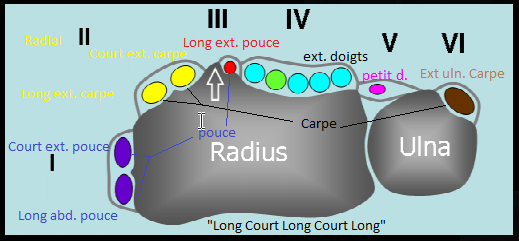

Anatomie

Syndrome de l’Intersection Distale

- Du aux mouvement repetés

- Croisement des 2e et 3e compartiment (Extenseurs du Carpe Vs Long Extenseur du Pouce)

- Se fait 4cm plus bas que le tubercule de Lister (bien couvrir sur IRM !)